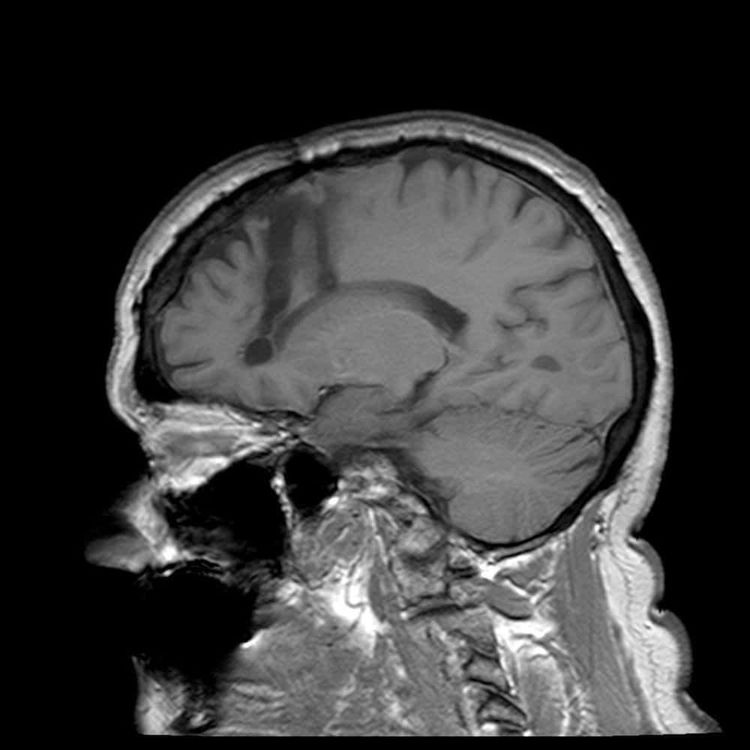

4. Лоботомия

Одним из самых мрачных эпизодов медицины XX века стала лоботомия.

Во время процедуры врачи повреждали лобные доли мозга пациента, иногда буквально вводя инструмент через глазницу. Считалось, что так можно лечить тяжелые психические расстройства.

Метод стал известен благодаря неврологу Уолтеру Фримену, но позже выяснилось, что он часто приводит к тяжелым изменениям личности и когнитивным проблемам.

Со временем от этой практики отказались.